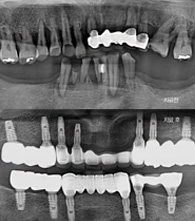

임플란트 누적 식립수[수술 성공률 98.1%]

18,576

Century Dental ClinicIt is conducted by a high-quality medical specialist..